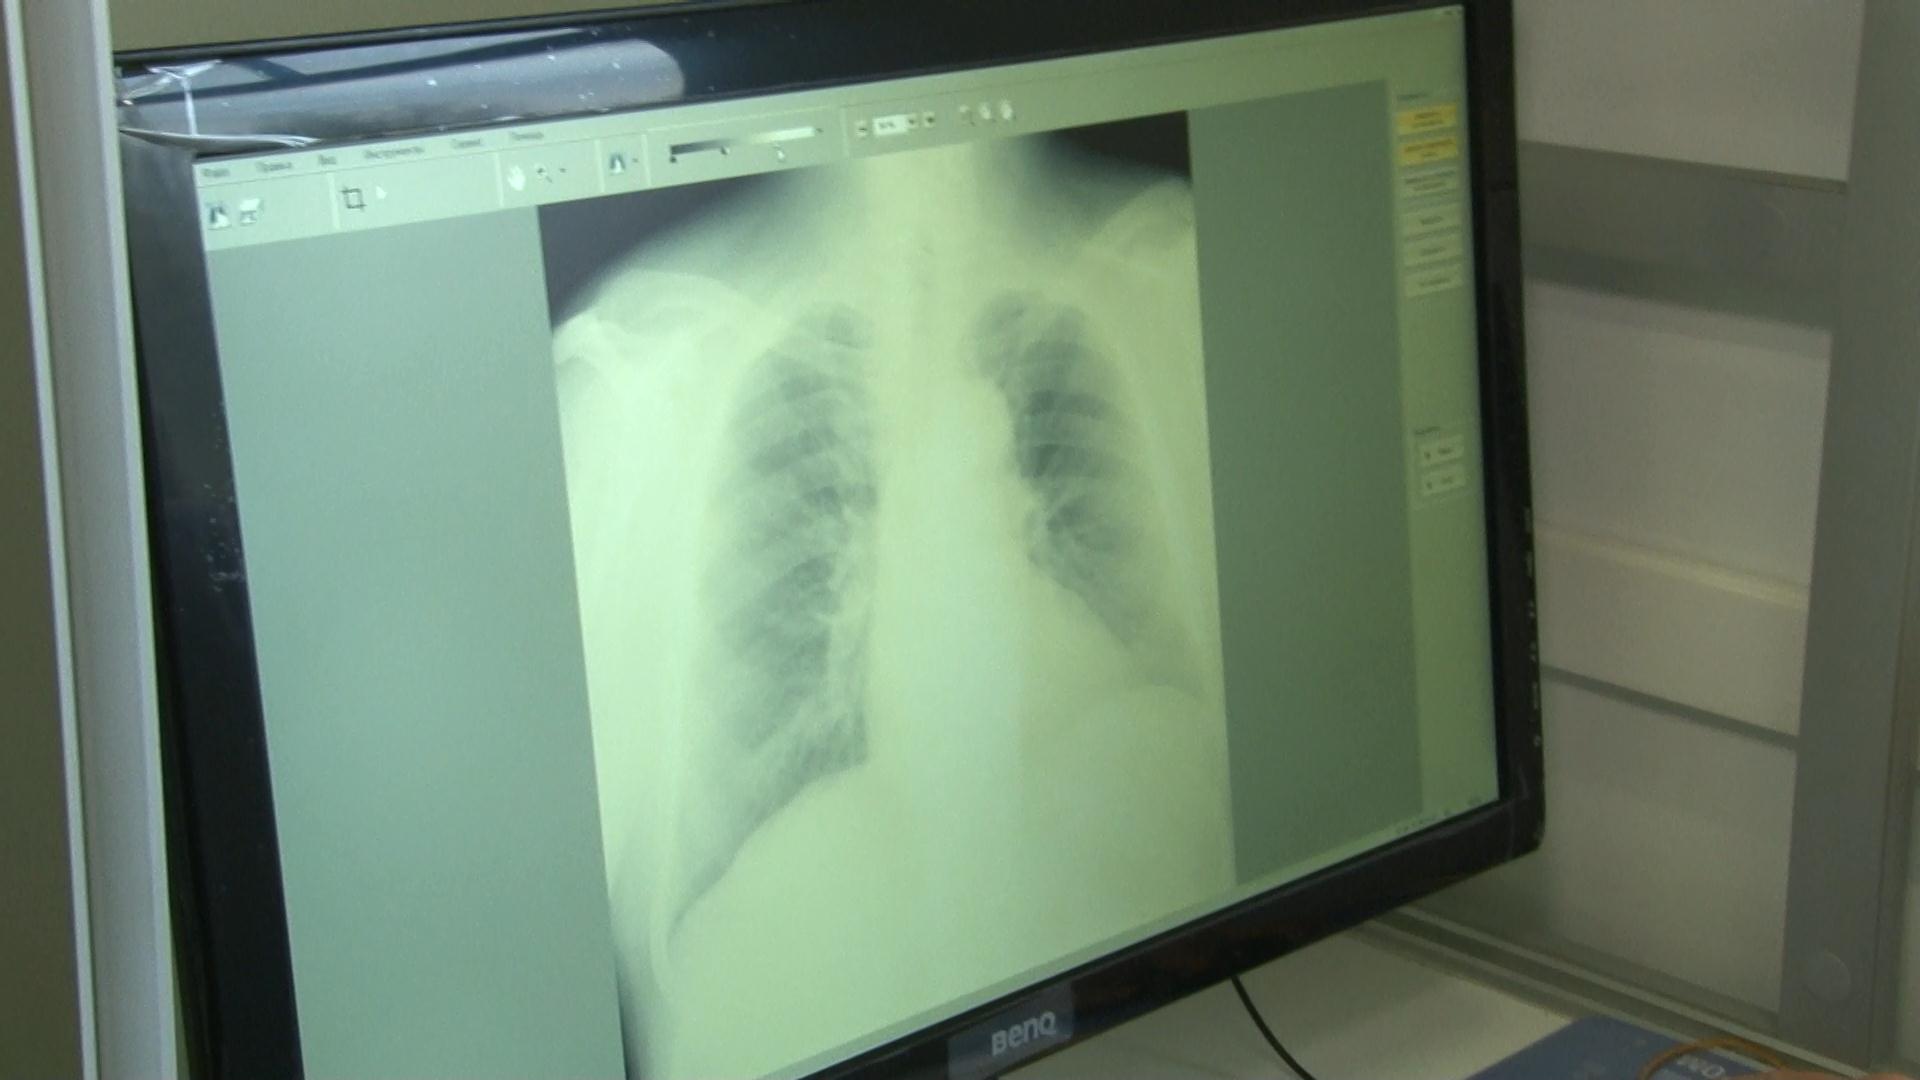

Новый передвижной цифровой флюорограф с минимальной лучевой нагрузкой поможет это исправить и позволит диагностировать на ранних стадиях не только туберкулёз, но и опухолевые заболевания, врожденные аномалии лёгких и профессиональные болезни.

«Новый передвижной аппарат сэкономит время и финансовые затраты сельских жителей. Он комфортный, удобный, здесь тепло и созданы хорошие условия как для пациентов, так и для работников. Диагностическое качество снимка имеет высокое разрешение и контрастность», - рассказала рентген-лаборант дубоссарской поликлиники Наталья Татарчук.